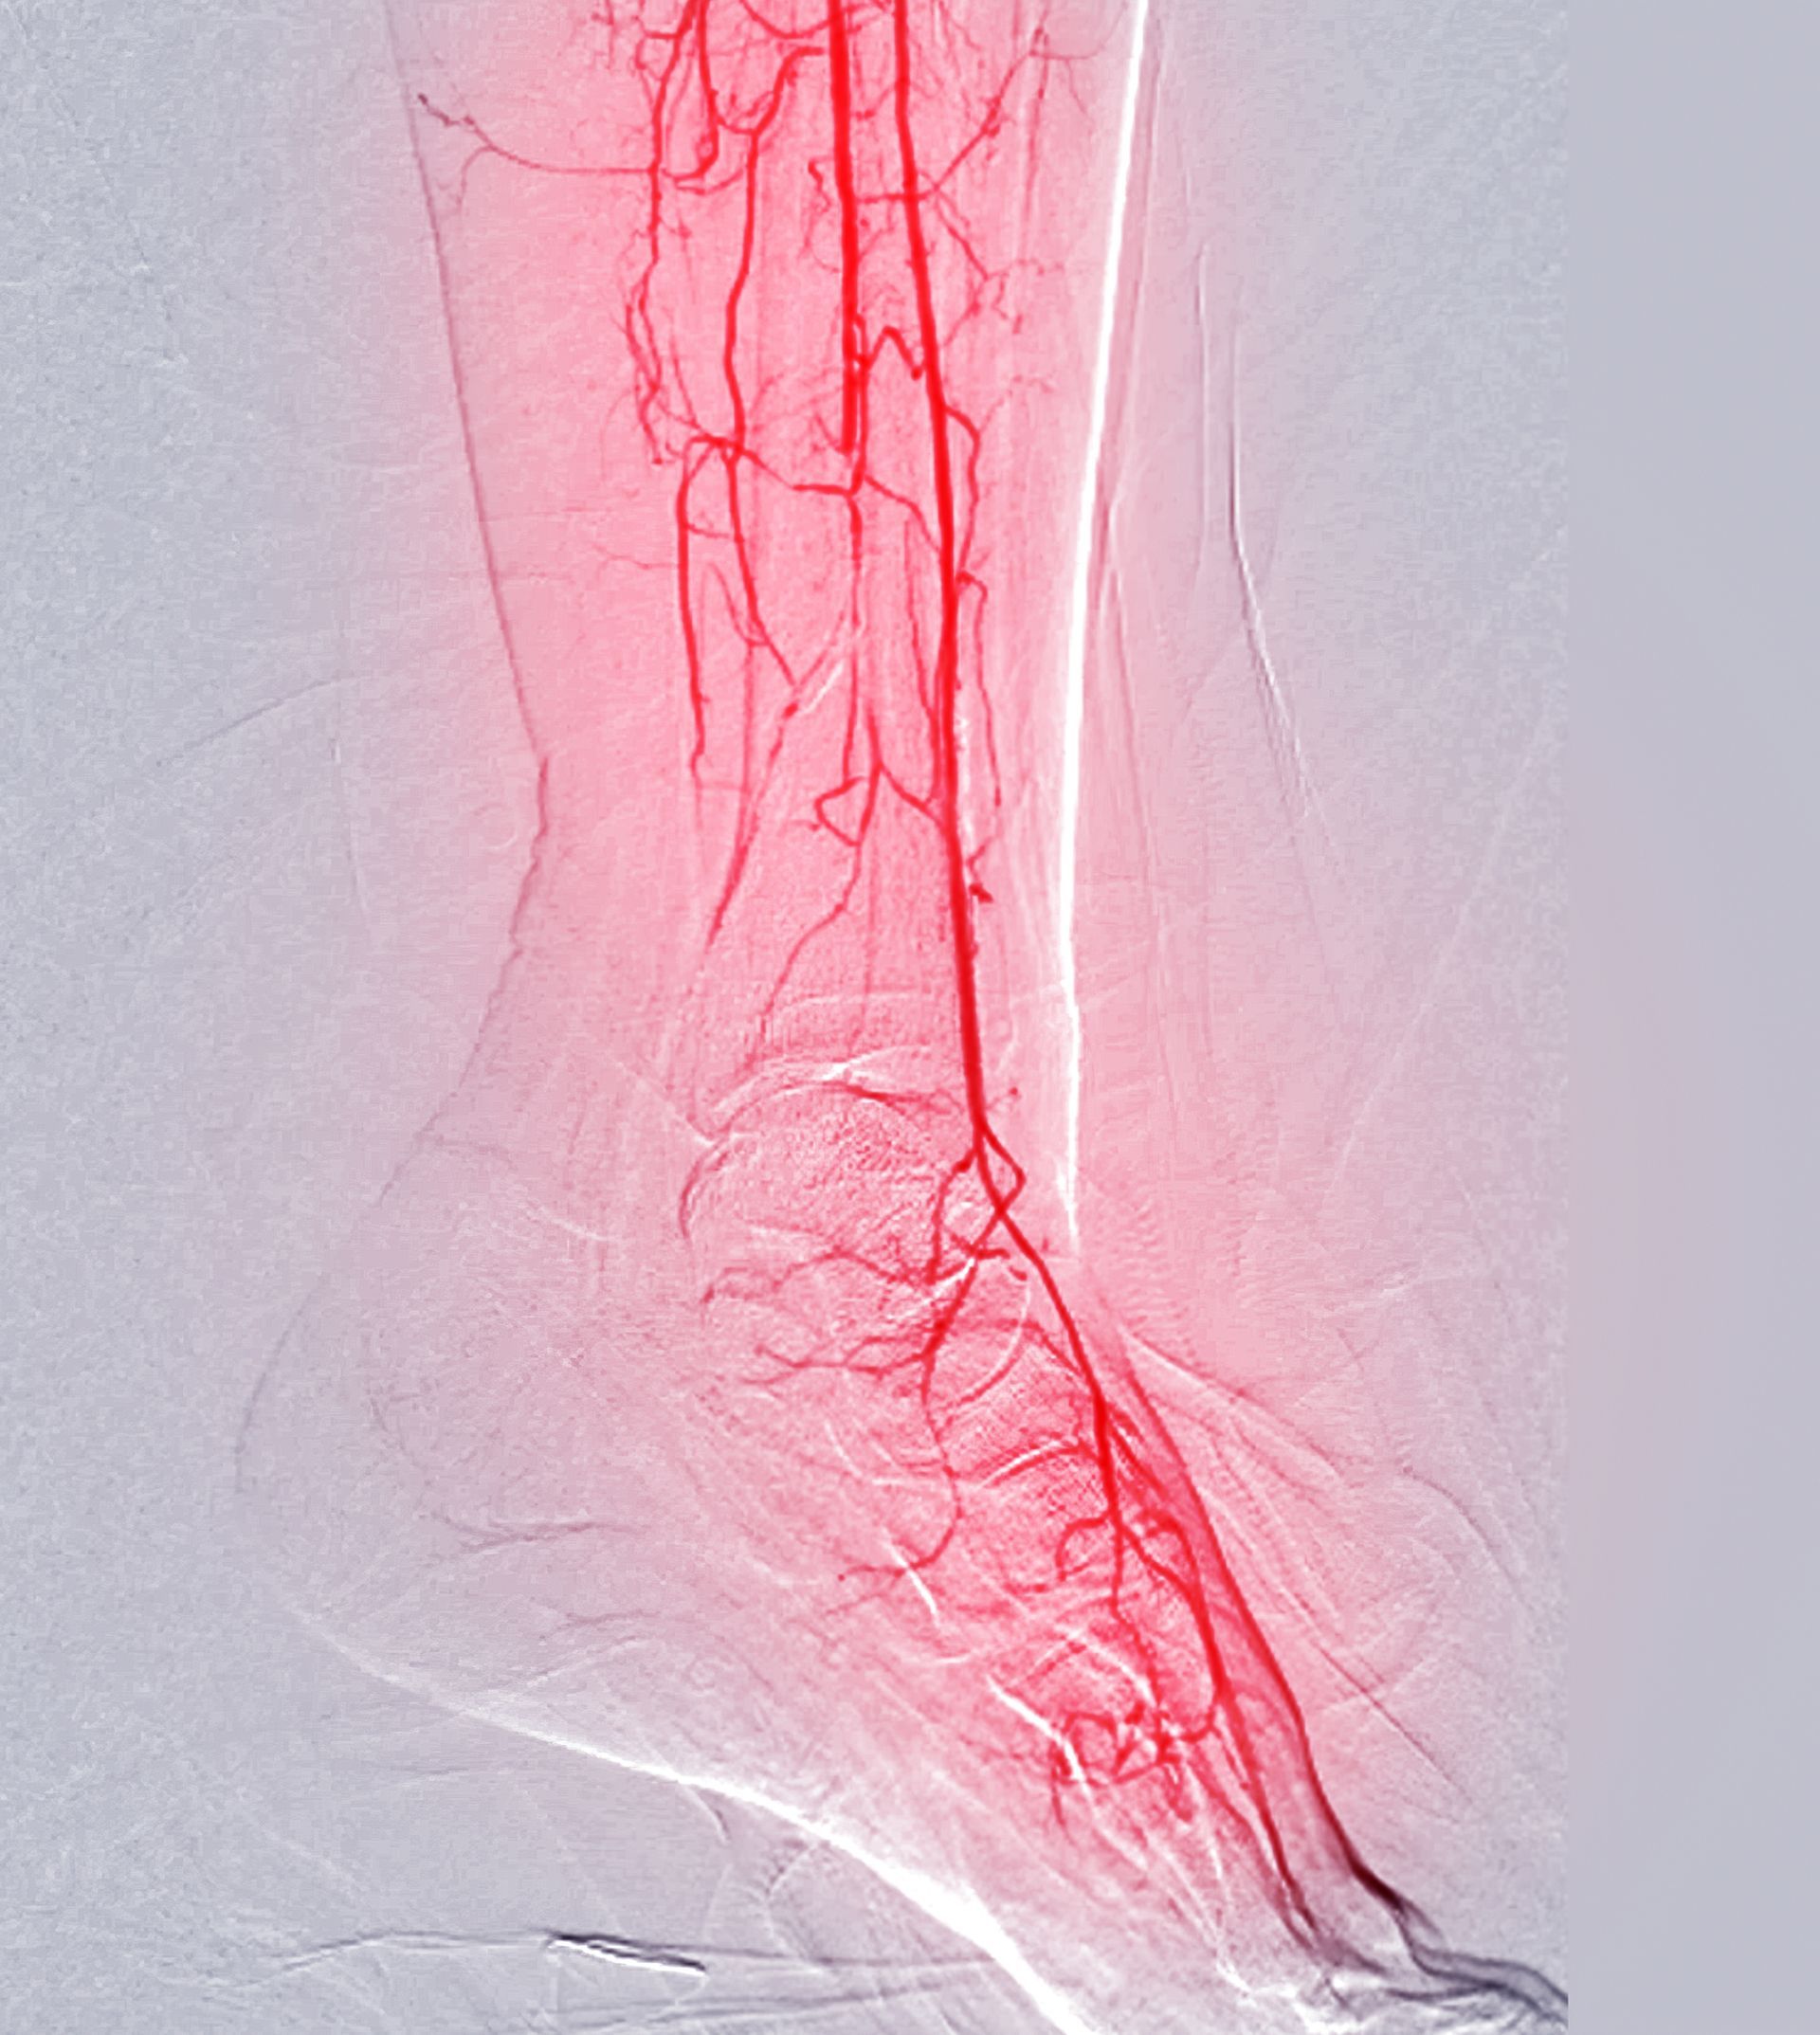

Peripheral Arterial Disease (PAD) is a circulatory condition that occurs when arteries supplying blood to the legs and feet become narrowed or blocked due to plaque buildup. This restricted blood flow can cause pain, cramping, numbness, or weakness in the legs—especially during walking or physical activity—and may lead to slow-healing wounds or, in severe cases, tissue damage. Early diagnosis and treatment are critical to preventing complications and improving quality of life.

We provide comprehensive vascular assessments to determine the severity of PAD using non-invasive diagnostic tools such as ankle-brachial index (ABI) testing and Doppler ultrasound. Based on your results, we create individualized treatment plans that may include lifestyle modifications, supervised exercise programs, smoking cessation guidance, cholesterol and blood pressure management, and medications to improve circulation. In advanced cases, minimally invasive vascular procedures may be recommended to restore proper blood flow.